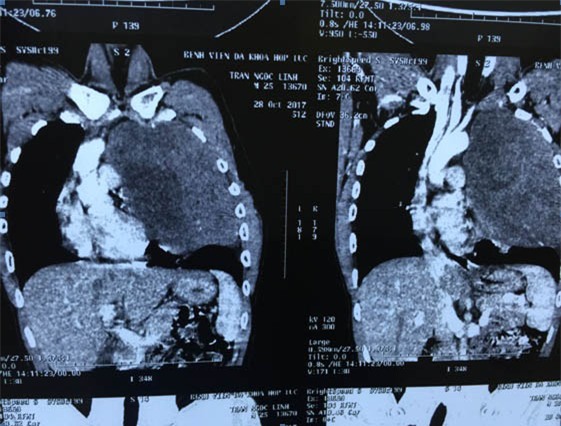

Khối u khủng che kín hết lồng ngực bệnh nhân.

Sau khi làm các thủ tục chụp chiếu, xét nghiệm bệnh nhân được chẩn đoán u thần kinh trung thất trên trái. Khối u chiếm toàn bộ khoang lồng ngực trái, kéo dài từ nền cổ tới gần sát cơ hoành, đè đẩy tim và các mạch máu lớn, làm xẹp nhĩ trái.

Cực trên khối u chèn ép vào bó mạch thần kinh cánh tay, cực dưới đè đẩy xẹp gần như toàn bộ phổi trái. Kết quả sinh thiết kim chẩn đoán giải phẫu bệnh kết luận u xơ thần kinh lành tính.